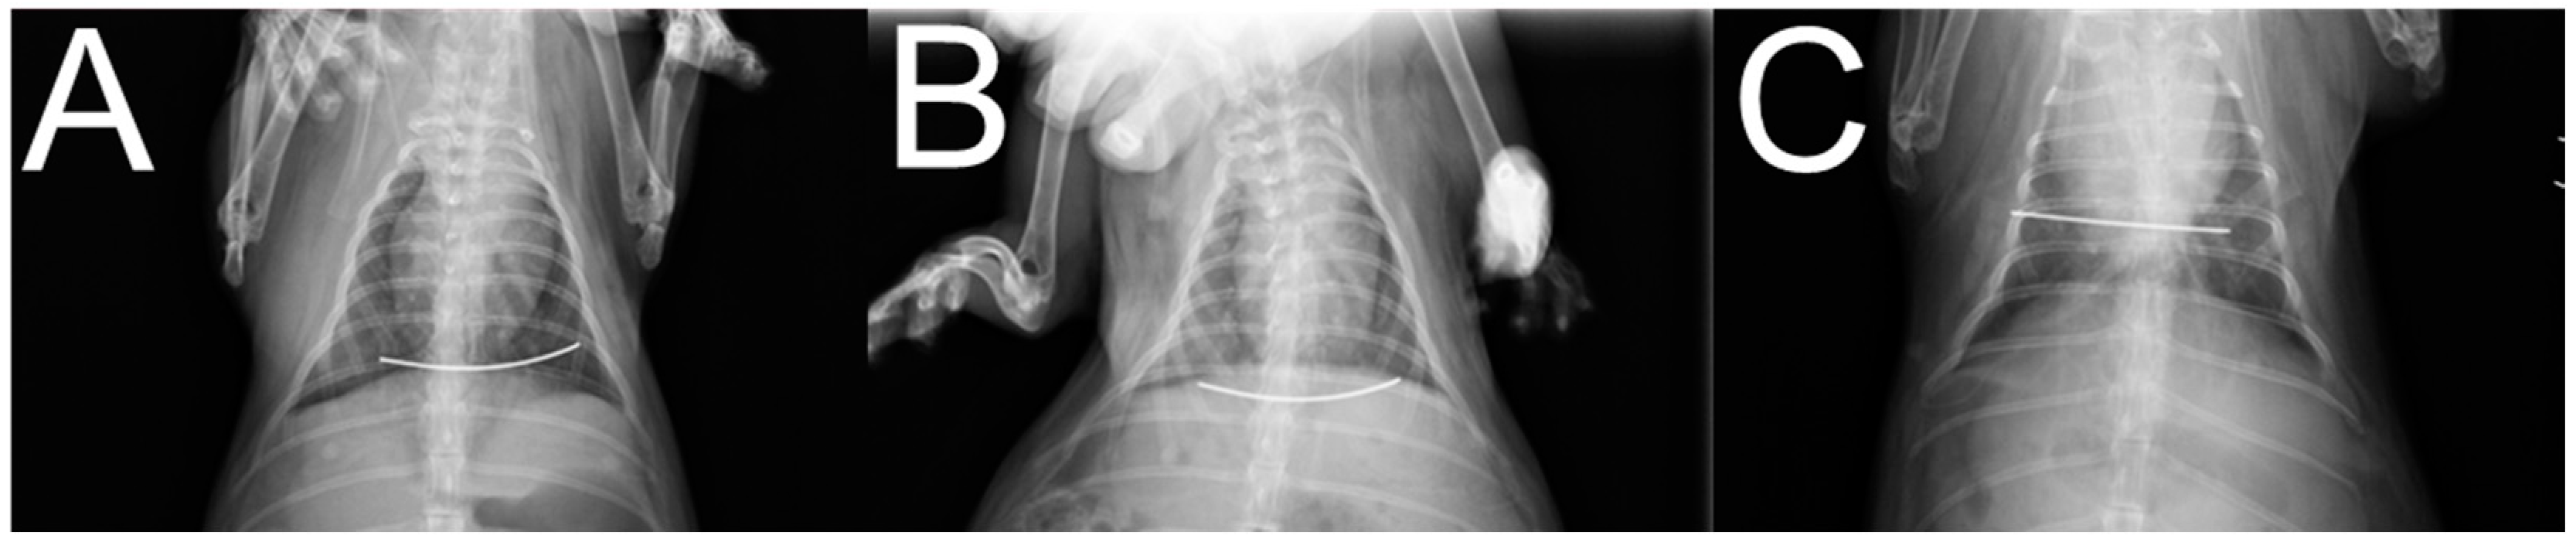

2.2. In Vivo Animal Studies